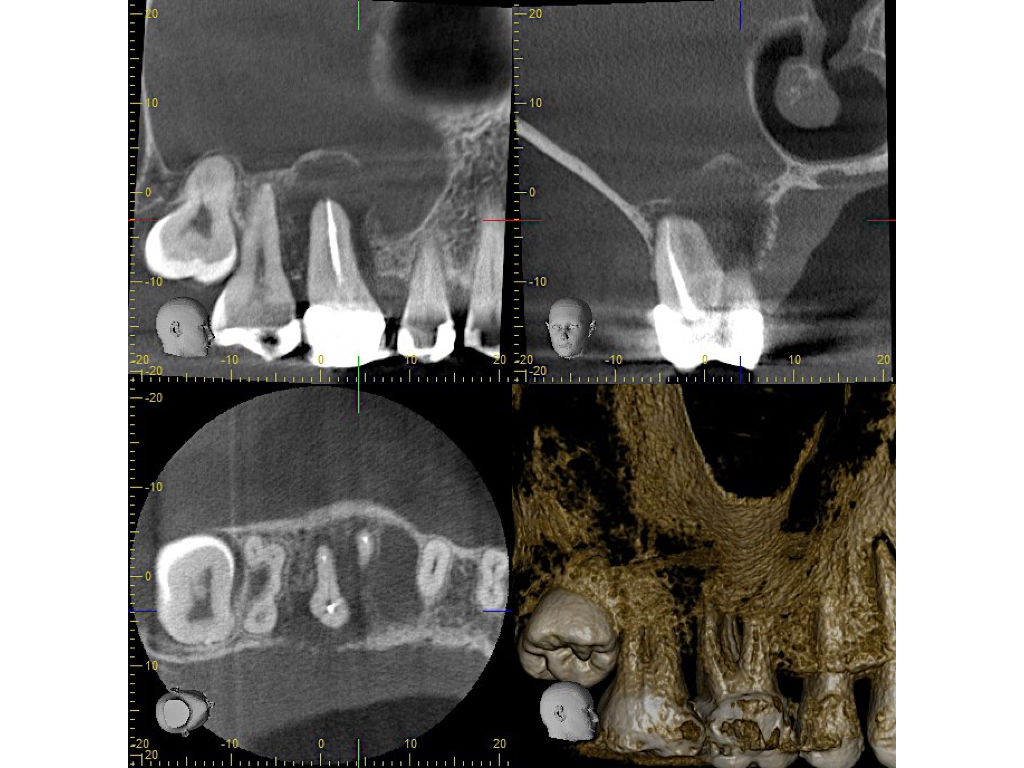

Healing?

DVT Ausgangssituation